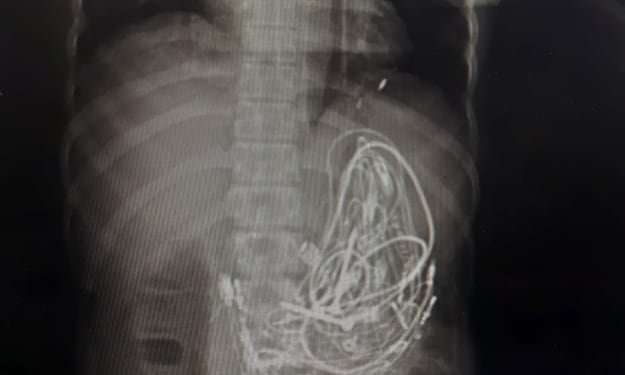

High-speed motorcycle accidents often come with a devastating price — a brutal collection of injuries that affect multiple systems of the body, a phenomenon known as polytrauma. A closer look at a case scan reveals the grim realities: multiple fractures of the rib cage, fractures of the pelvis, and severe spinal injuries where vertebrae are both broken and misaligned. To make matters worse, fractures of the facial bones, including those of the nasal structures, are commonly observed, adding to the extensive trauma profile.

Beyond the obvious fractures, internal organ damage is a significant and life-threatening concern. The areas of redness and swelling observed in the chest and pelvic regions often point to soft tissue trauma or internal bleeding. Vital organs such as the liver and spleen are highly susceptible to lacerations, and injuries to large blood vessels like the aorta can lead to rapid blood loss, making immediate surgical intervention critical. Without swift and expert medical care, survival becomes a race against time.

The story told by the medical scans — with shattered ribs, broken pelvises, dislocated vertebrae, and battered faces — is not just a collection of injuries; it is a stark warning. For every rider who takes to the road, these images should serve as a powerful reminder: Speed thrills, but safety saves.